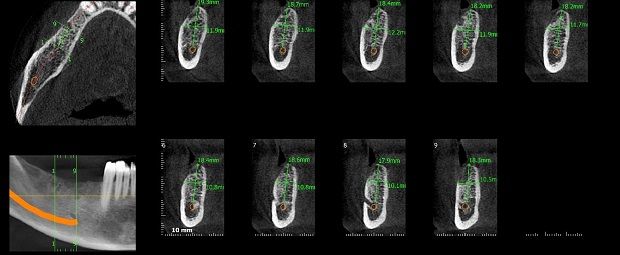

A las técnicas tradicionales como la radiología, sumamos estudios de avanzada para asistir a las prácticas de alta complejidad médica incluyendo la Tomografía Computada Cone Beam el más moderno sistema de imágenes odontológicas y maxilofaciales.